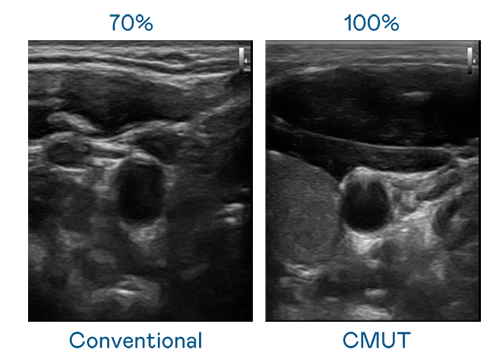

CMUT 技术是一种用电容式微机电元件来产生超音波讯号的技术。与传统 PZT 压电式技术相比,CMUT 频宽增加 30%,更宽频的超音波讯号让影像解析度大幅提升,是实现高影像品质医疗超音波扫描、促进精准医疗发展的关键技术。

大频宽带来超清晰影像

超音波影像的解析度高低,首先取决于探头能发出的讯号频宽。J9集团 CMUT 可提供高清晰的超音波讯号,提供高频宽、高灵敏度、影像纹理细节更高的超音波影像,协助医护人员缩短影像判读时间及利用精准的医疗影像进行诊断。